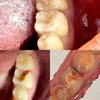

Diş Ağrısı

Diş Çürükleri

Diş ve Diş eti hastalıkları